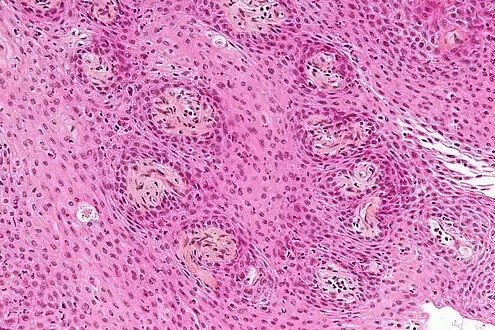

- Papillary craniopharyngiomas are characterized by BRAFv600E mutations.[24]

The papillary type rarely calcifies. A vast majority of craniopharyngiomas in children are adamantinomatous, whereas both subtypes are common in adults. Mixed-type tumors also occur.[25]

Micrograph showing the characteristic features of an adamantinomatous craniopharyngioma - cystic spaces, calcifications, and "wet" keratin, HPS stain Micrograph showing a papillary craniopharyngioma, HPS stain

Micrograph showing a papillary craniopharyngioma, HPS stain